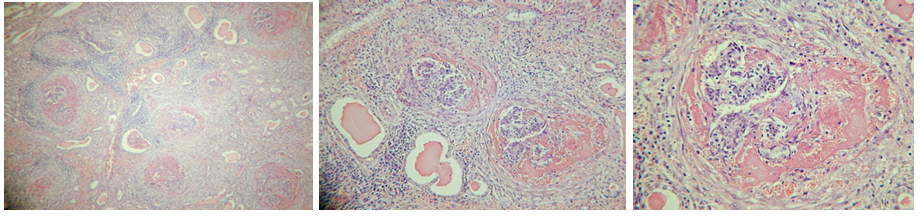

27. Cholangitis et pericholangitis chronica hyperplastica (Coccidiosis hepatis cuniculorum)

Description: In normal liver parenchyma, irregularly shaped areas bordered by fibrinous tissue are seen. Areas indicate hyperplasia of bile duct wall. Proliferation of epithelium, which is forced into papillary folds, simulates adenomatous hyperplasia.

Etiology: Coccidiosis is an infection by protozoan parasite eimeria or isospora.

Pathogenesis: Inflammation of the biliary tract. Coccidia are obligatory intracellular parasites which develop within the cytoplasm of epithelial cells, which result in death of affected cells. Loss of epithelial cells result in villus atrophy in the intestine. Chronic infection results in hyperplastic epithelium.